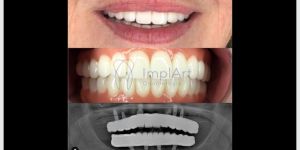

A prótese protocolo consiste em uma prótese total fixa, que é parafusada sobre implantes dentários. Esses implantes são inseridos cirurgicamente no osso maxilar ou mandibular, de modo a funcionar como raízes artificiais. Esse processo inclui procedimentos protéticos cuidadosos para garantir uma adaptação de próteses perfeita. A cirurgia de implante dentario pode ser realizada junto a enxerto ósseo, caso seja necessário, na grande maioria dos casos.

As próteses protocolo são essenciais para a reabilitação protética, pois restabelecem não apenas a função mastigatória, mas também a estética facial e o conforto. Além disso, esses protocolos de prótese são fundamentais para melhorar a pronúncia e a confiança ao sorrir. Os procedimentos protéticos minuciosos garantem que o paciente obtenha uma reabilitação bem-sucedida e duradoura.

Pacientes geralmente esperam uma melhora instantânea na função e estética após a colocação de suas próteses. Importante compreender que o tratamento envolve etapa de cirurgia de implantes dentarios, uso de prótese provisória, e após cicatrização dos implantes, e elaboração da protese fixa sobre implantes. Atualmente a Prótese de Zircônia é a mais moderna! a realidade muitas vezes inclui um período de adaptação à nova estética do sorriso e à nova mastigação.

Planejamento computadorizado desempenham um papel crucial no planejamento e na execução precisa dos implantes. Eles garantem a posição correta dos implantes, o que é essencial para a estabilidade e longevidade da prótese. Diversos estudos apontam que o uso de guias personalizados confeccionados com tecnologia CAD/CAM, pode reduzir significativamente as complicações pós-operatórias pela precisão que oferecem.

Além dos guias de prótese, as técnicas modernas em próteses têm revolucionado o campo da reabilitação oral. Entre as mais renomadas estão as que utilizam scanners intraorais e impressoras 3D para criar modelos precisos e personalizados. Estas tecnologias não apenas melhoram a adaptação da prótese, como também diminuem o tempo de consulta e o desconforto do paciente. A implementação de protocolos de prótese que incorporam essas inovações garante um processo de reabilitação mais eficiente e confortável. Na Clínica ImplArt o uso da tecnologia é uma realizada diária pois a Clínica utiliza modernos sistemas com braços robóticos que fazem a impressão de próteses provisórias, ou próteses protocolo de Zircônia de alta qualidade e durabilidade.